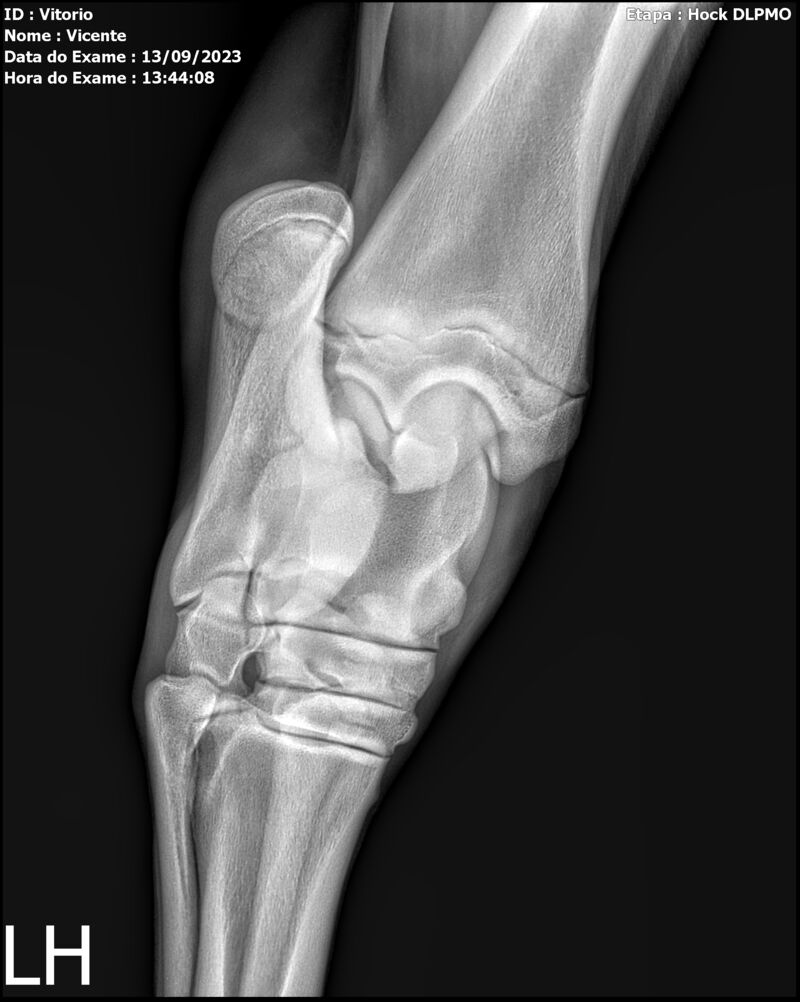

LOTE 13

THUNDER ZC

Raça: BRASILEIRO DE HIPISMO

Sexo: MACHO - POTRO

Nascimento: 17/09/2022

Altura Aproximada: 1,54

Pel.: CASTANHO

Registro: EM AND

Vend.: VICENTE CONTE

Local : PORTO FELIZ/SP